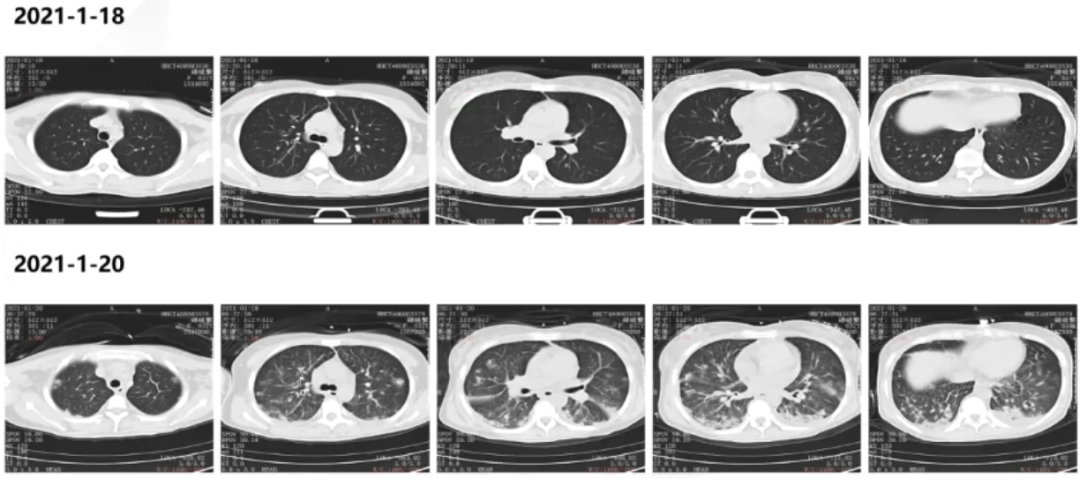

患者1月18日胸部CT基本正常,但1月20日胸部CT示两肺多发实变伴结节影(图1)。

图1 患者入RICU前后胸部CT对比